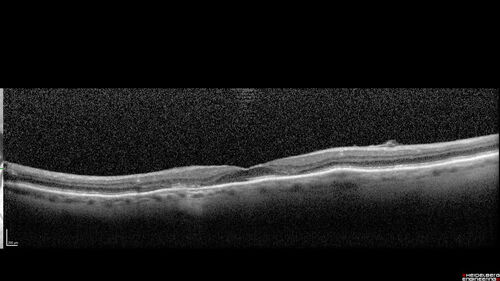

Hydroxychloroquine (plaquenil) Toxicity - Advanced

78 year old female No visual complaints referred for evaluation

Medical Hx: Rheumatoid Arthritis. Atrial Fibrillation. Benign Intracranial Hypertension. Sjogrens Syndrome. Osteoporosis.

Systemic Meds: PLAQUENIL (Stopped 2 months ago). Leflunomide. Lidocaine. Gabapentin. Vitamin D. Multaq. DILTIAZEM.

1993 Plaquenil Initially 400 mg /day (9 mg/kg/day x 18 years) then 2011 200 mg daily - (4.6 mg/kg/day x 10 years) STOPPED 3/2021

The patient weighs 100 lbs and is 4’ 2” tall - Images are from 3/2021 and 5/2022

There was no progression 1 year after stopping plaquenil in this patient.